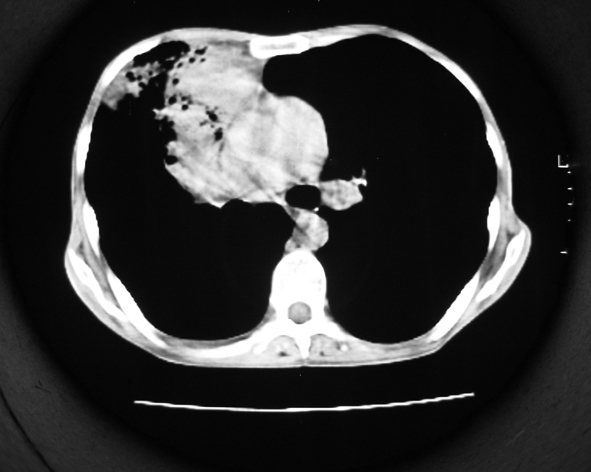

男53岁,咳嗽气短,以往身体健康.

右肺上叶多发多形态空洞及增殖灶,可见团块钙化,胸膜肥厚、粘连,考虑继发型肺结核可能性大

1.右肺上叶干酪性肺炎,2。肺气肿,肺大泡

右肺上中叶结核干酪性肺炎

右肺中上叶干酪性肺炎。

支持右上肺继发性肺结核并干酪性肺炎,右肺大泡,左肺代偿性气肿。